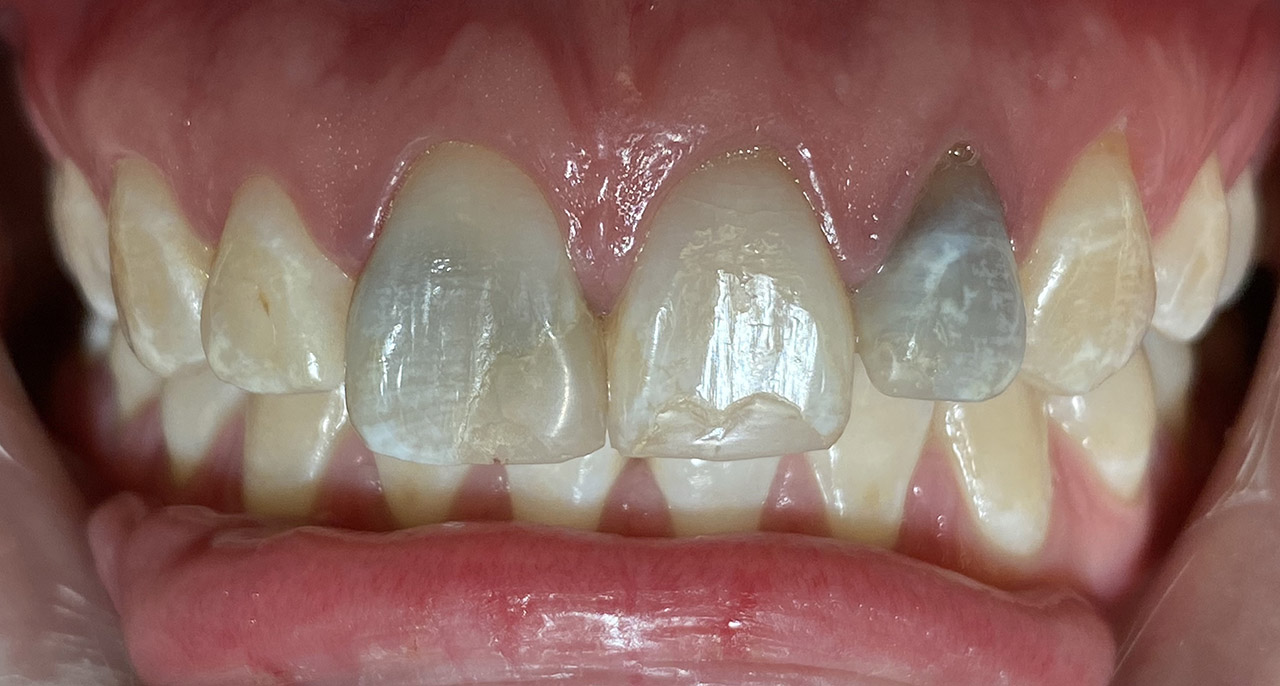

Internes und Externes Bleaching (Bleichen):

Nach Unfall mit E-Scooter unbefriedigendes Ergebnis der Erstversorgung (alio loco). Therapievorschlag: Stiftzähne?

Unsere minimalinvasive Therapie: Revision der Wurzelbehandlungen, danach internes und externes Bleaching, adhäsive Kunststoffüllungen in Schichttechnik. (Titel meiner Diplomarbeit 2003 “Die Vermeidung von Extraktion und Wurzelspitzenresektion durch zeitgemässe Endodontie in der Privatpraxis”)